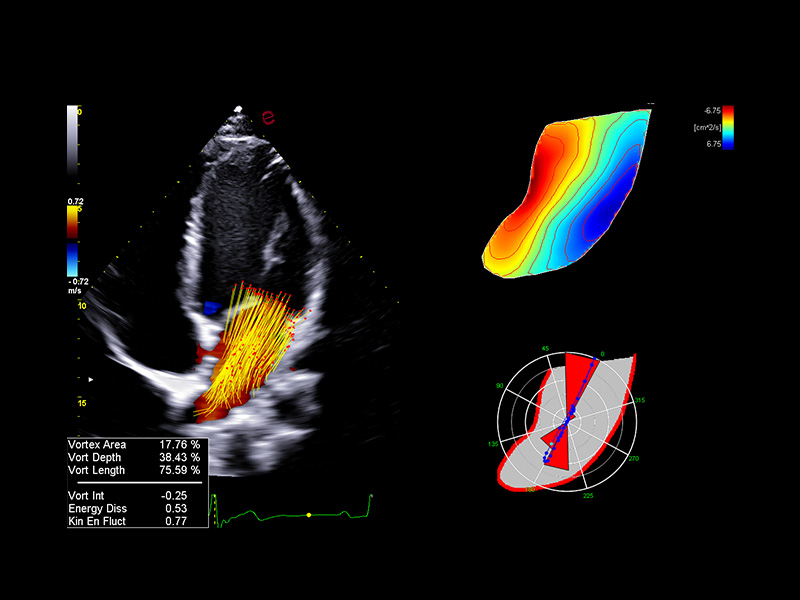

Innovative hemodynamic assessment with HyperDoppler

Esaote’s HyperDoppler technology provides an advanced visualization of intracardiac blood flow dynamics, offering clinicians an intuitive understanding of complex hemodynamics that goes beyond conventional Doppler imaging. By generating real-time vector maps, streamlines, and vortex formations, HyperDoppler enables the detailed assessment of diastolic function, ventricular dyssynchrony, and valvular abnormalities.

This unique flow visualization supports earlier detection of subtle dysfunction, particularly in challenging cases such as heart failure, prosthetic valve evaluation, and structural heart disease. HyperDoppler’s zero-click, visually rich interface enables faster, more comprehensive exams, allowing cardiologists to make more informed clinical decisions.